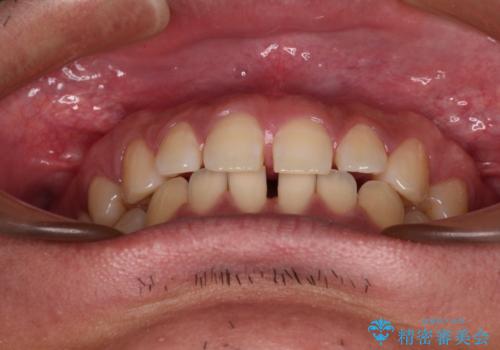

- 上下前歯の隙間を気にして来院された患者様です。

飲み込みや話をするときに舌を突出させる癖が強くあり、それが原因でスペースが空いていました。

舌癖を改善するためのトレーニングを行いながら、ワイヤー装置を用いて前歯の隙間を閉じていくこととしました。